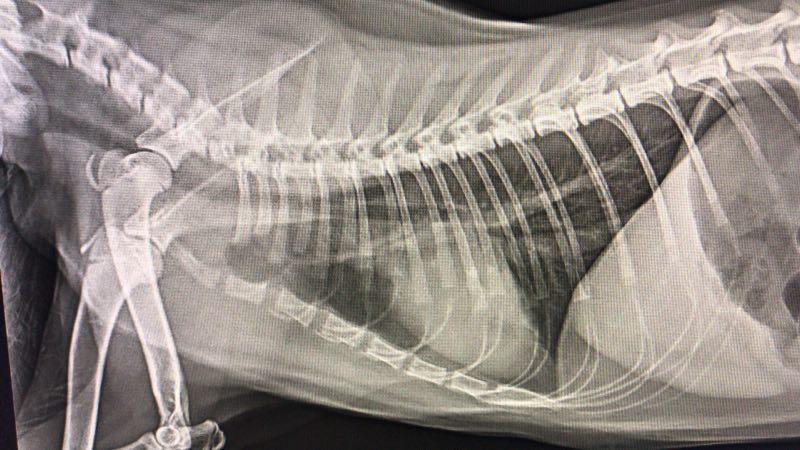

一般给猫咪做胸部X光检查和血常规来确定猫咪是否肺炎。也可通过超声波来检测肺部的感染。

▲未感染肺炎的x光